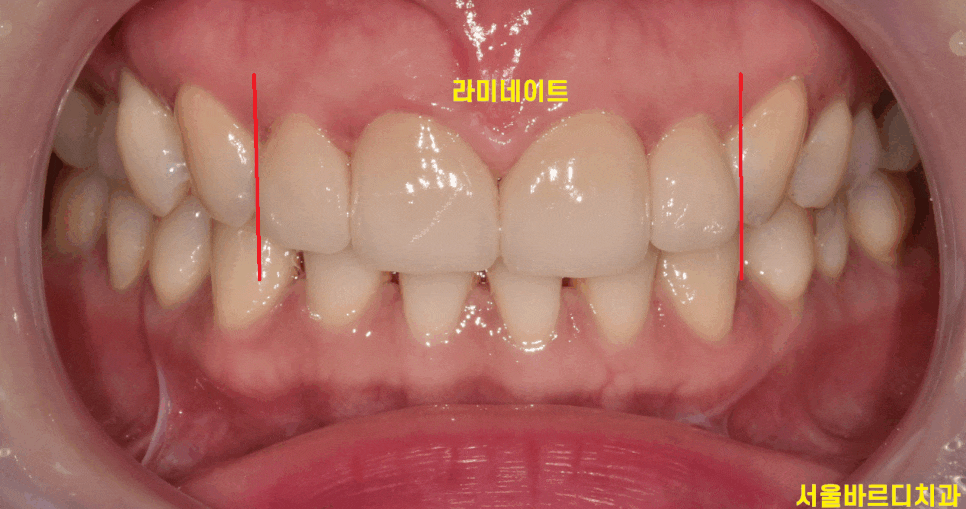

환자분은 바로 옆 대문니가 크다 보니

치아가 각도상 비틀어져 있어서

유독 작게 보이네요.

반대편 같은 치아의 경우 각도는 제대로 되었지만

이 역시 왜소치에 속합니다.

어떤게 라미네이트일까요~??

감쪽같죠~??

보철이라 해서 티가 나면 안됩니다.

어떤것이 라미네이트 치아인지 감쪽같게

만들어 드리는게 기술력이죠!!!

작은 치아로 고민하시던 환자분은

앞니 4개 치아 사이즈를 재분배하여

컴플렉스 극복시켜 드렸습니다.